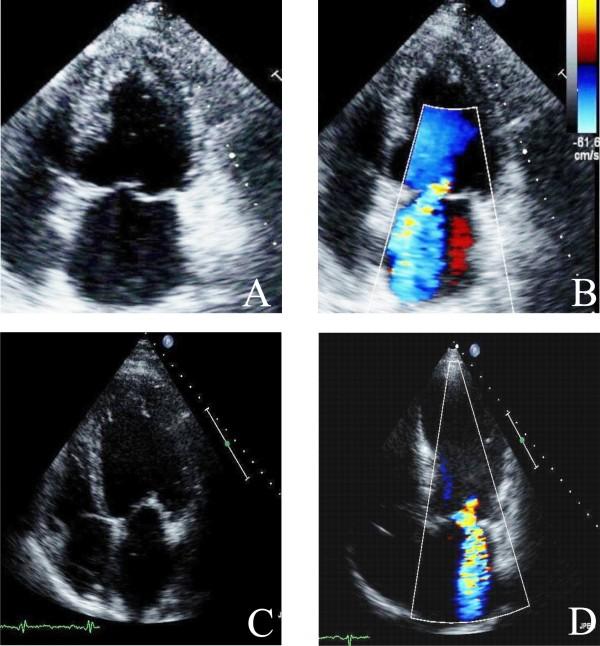

Aortic stenosis and mitral regurgitation, patent foramen ovale, interatrial septal defect, atrial fibrillation and perivalvular leak, are now amenable to percutaneous treatment. These percutaneous procedures require the use of Transthoracic (TTE), Transesophageal (TEE) and/or Intracardiac echocardiography (ICE). This paper provides an overview of the different percutaneous interventions, trying to provide a systematic and comprehensive approach for selection, guidance and follow-up of patients undergoing these procedures, illustrating the key role of 2D echocardiography.

主动脉瓣狭窄、二尖瓣反流、卵圆孔未闭、房间隔缺损、心房颤动及瓣周漏,目前均适合经皮治疗。这些经皮手术需要使用经胸超声心动图(TTE)、经食管超声心动图(TEE)和/或心内超声心动图(ICE)。本文概述了不同的经皮介入治疗,试图为接受这些手术的患者提供一种系统、全面的选择、指导及随访方法,并阐述二维超声心动图的关键作用。